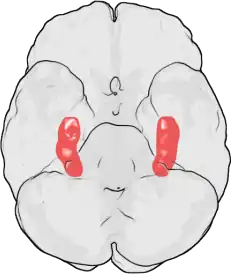

Lage der Hippocampi (rot) im menschlichen Gehirn:

Ansicht von unten (die Stirn liegt im Bild oben)

Beteiligt beim deklarativen Gedächtnis ist der gesamte Neocortex, beim episodischen Gedächtnis insbesondere der rechte Frontal- und der Temporalcortex, beim semantischen Gedächtnis speziell der Temporallappen.

Beteiligt, insbesondere beim Vorgang der Speicherung, sind jedoch auch subkortikale Regionen, wie das limbische System, vor allem das mediale Temporallappensystem, der Hippocampus und angrenzende Gebiete. Diese sind im sogenannten Papez-Neuronenkreis zusammengefasst. Oft zitiert wird der Fall des Patienten HM, dem zur Therapie schwerer Epilepsie beide Hippocampi entfernt wurden. Zwar wurde die Epilepsie geheilt, der Patient zeigte jedoch nach der Operation eine schwere anterograde Amnesie: Er konnte sich nichts Neues mehr merken. Der Zugriff auf vor der Operation erworbene Gedächtnisinhalte war hingegen nicht beeinträchtigt.